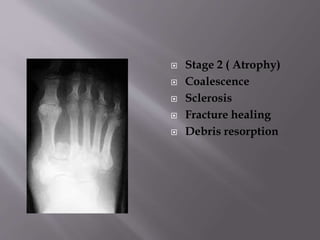

 Stage 2 ( Atrophy)

 Coalescence

 Sclerosis

 Fracture healing

 Debris resorption

 Stage 2( Atrophy)  Coalescence  Sclerosis  Fracture healing  Debris resorption